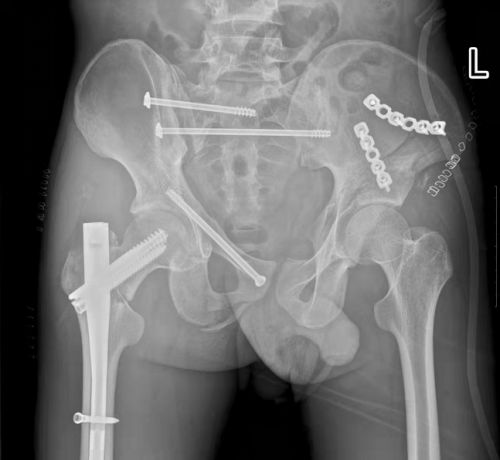

术前x线可见多处骨折。

术后,骨折断端固定牢靠。

创伤骨病科主任盛斌指出:患者骨盆存在多处骨折,失血性休克明显,由于此处解剖结构的复杂性和特殊性,传统手术方式往往手术时间长、创伤大、出血多。而如果不能早期对骨盆环进行稳定,骨折端及其他部位的静脉丛可反复出血,导致休克加重,危及生命。患者刚做了开腹手术,如果再进行传统骨折切开复位手术,风险极高。

经过反复讨论研究手术方案,在麻醉科、手术室的配合下,盛斌主任带领创伤救治团队为小张施行复杂骨盆及股骨骨折微创复位内固定手术。术后,在急诊ICU等多学科团队的积极治疗和精心护理下,患者病情好转出院。